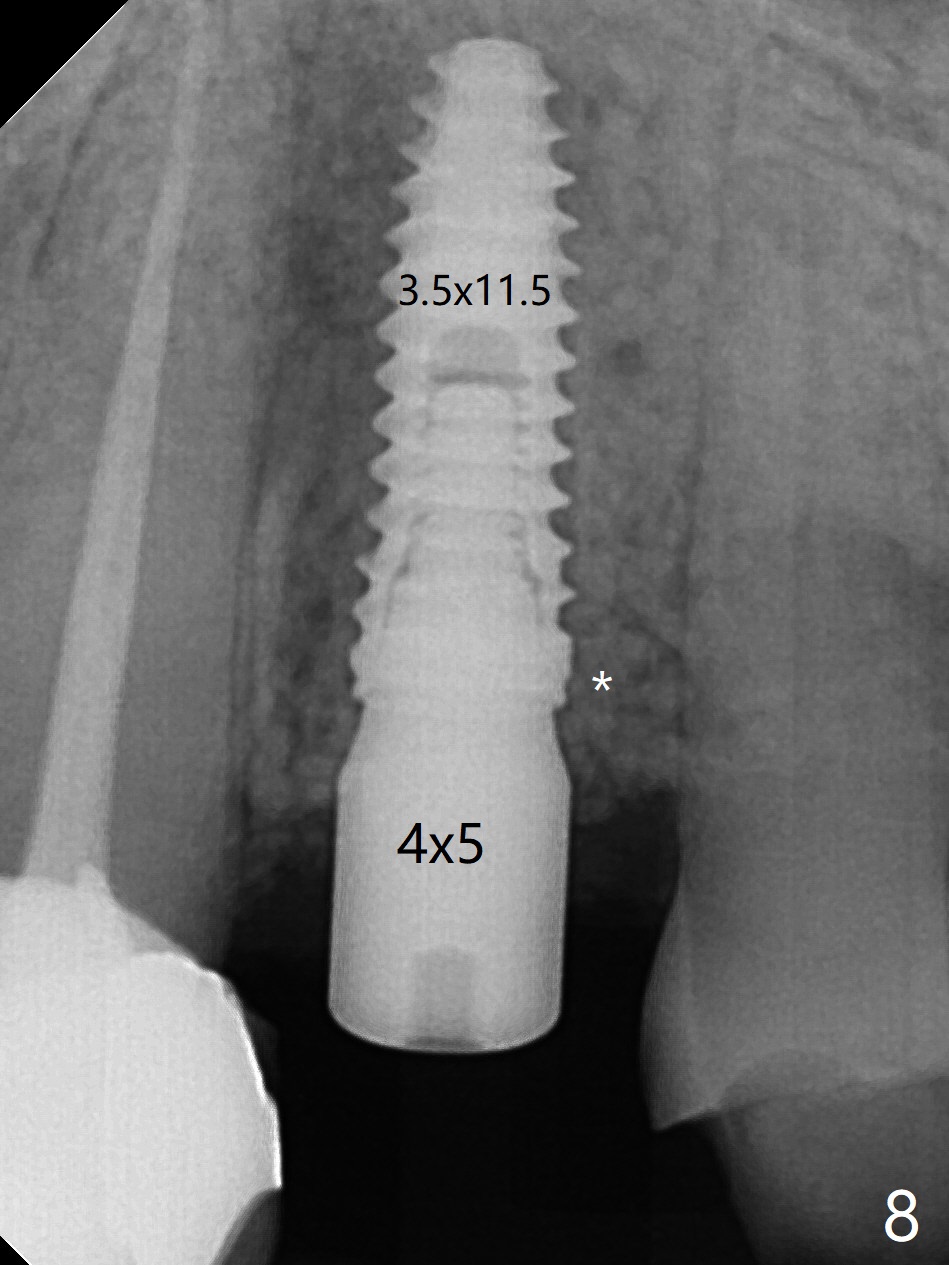

植骨后6个月牙槽窝愈合正常,角化龈和牙槽嵴都宽(图一),导板种植好像不需要切口。利用导板植入,但是离尖牙牙根很近(图二,三)。取出植体后,准备切开改变钻洞方向(图四,五),结果效果不错(图六,七),腭侧骨壁低,安置愈合基台,植骨(图八:*),覆盖胎盘膜,缝合。